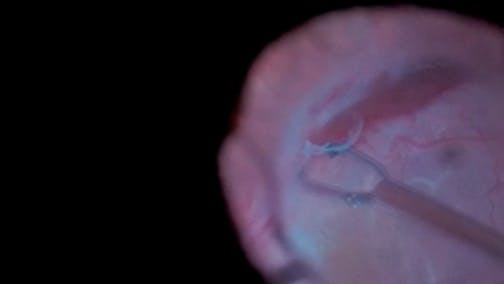

Unpleasant Surprise

Stratos Gotzaridis, MD